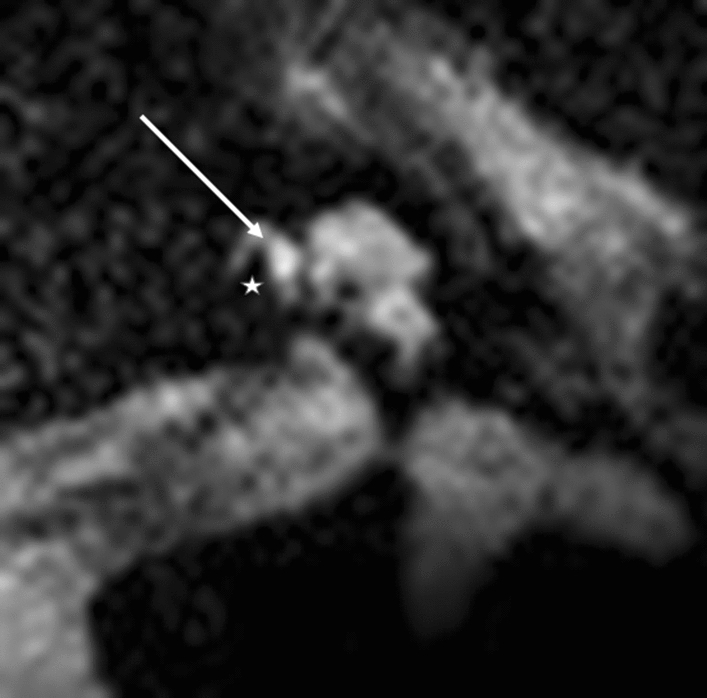

Figure 1.

Straight electrodes, basal turn. (a) Flex 28, (b) SlimJ. Star represents diminishing electrode signal, arrow represents basilar membrane.

For the basal turn, a diminishing signal indicates the electrode localisation. At the lateral portion of the cochlea, each electrode was positioned depending on its design: either laterally, without any further lateral T2 signal (Fig. 1a,b), or more medially positioned with a T2 signal (Fig. 3). Lateral diminishing signal varied depending on electrode design: Flex 28 was round, and SlimJ laterally flatter. As a second indicator, a basilar membrane was visible. This basilar membrane diminishing signal allowed definitive estimation of the electrode location in the scala tympani or scala vestibuli.